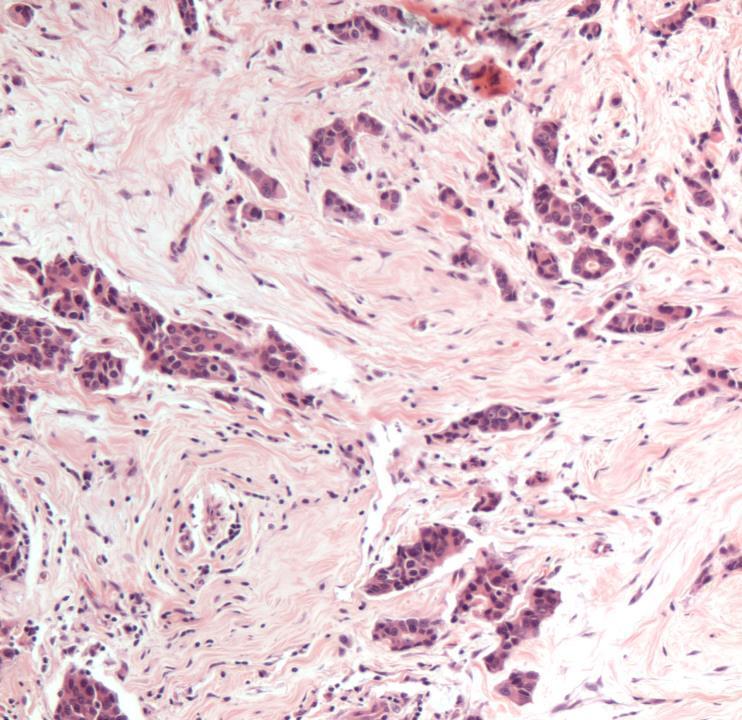

Case 7

◼ Invasive ductal NST carcinoma, grade 1

◼ Sclerosing adenosis